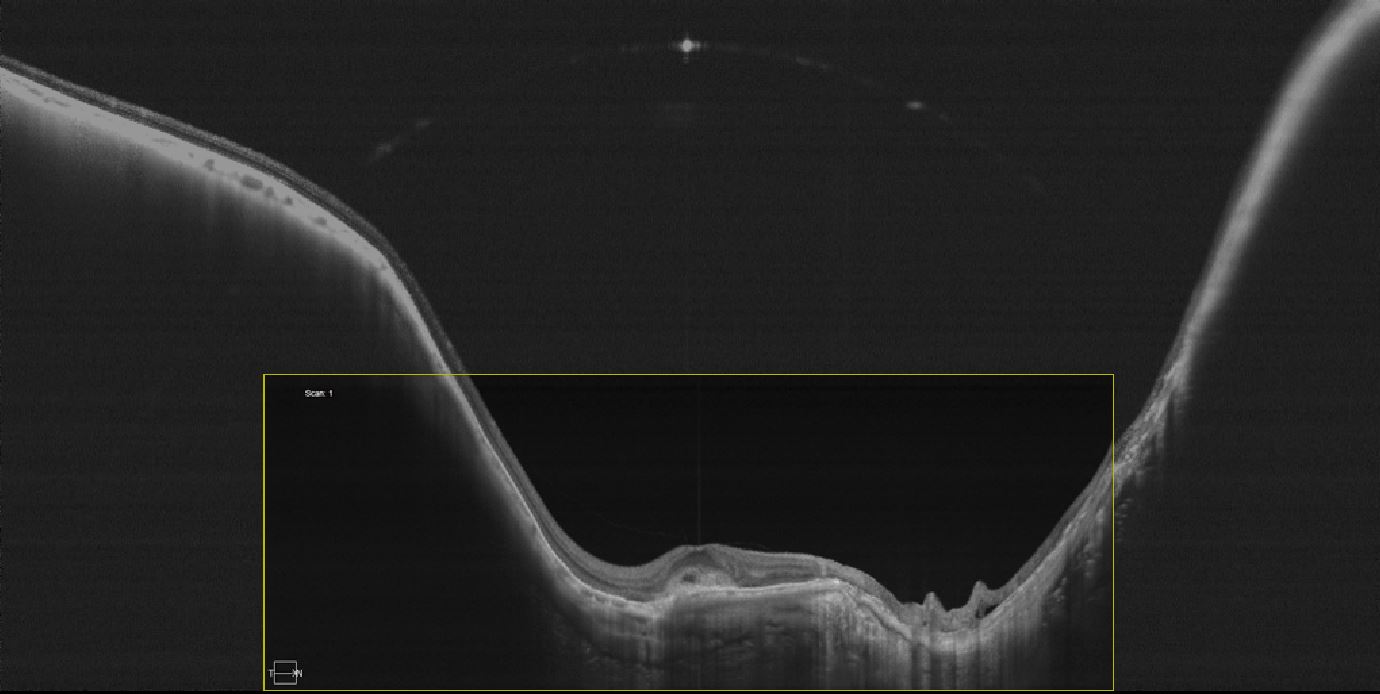

Малюнок 2. Скан 23 мм Canon OCT-S1 у порівнянні зі стандартним ОКТ сканом. Широкопольний ОКТ візуалізує набагато більшу ділянку сітківки, що не дозволить пропустити патологію периферії.